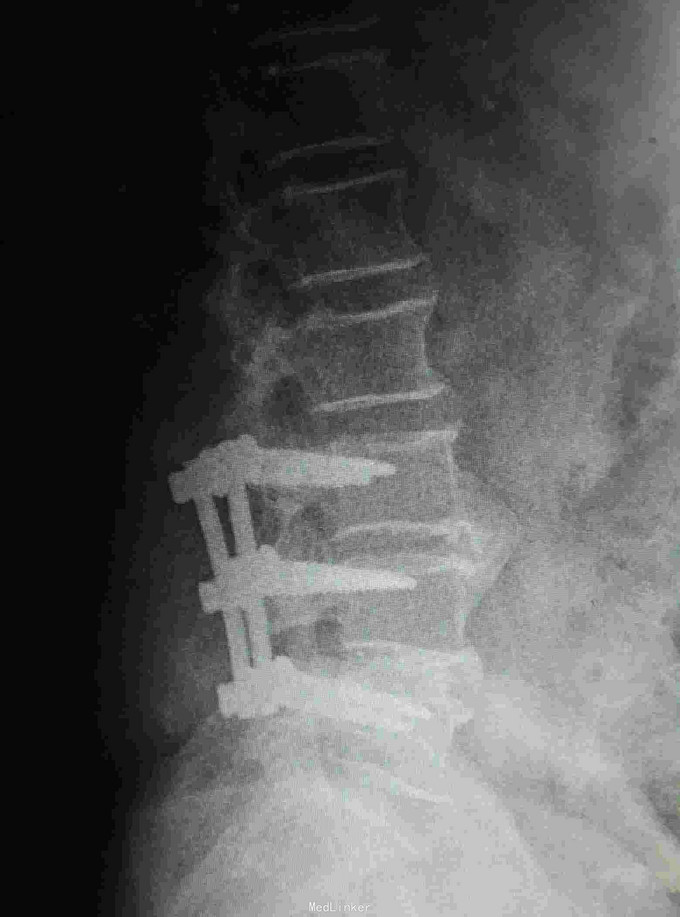

腰痛伴左下肢疼痛不适半月 患者无明显诱因出现腰痛,伴有沿左大腿根部后侧至外踝的疼痛,行走加重,休息可有缓解,期间未做特殊处理,外院核磁提示椎管内肿物,为求进一步诊治入我院。

查体:脊柱生理弯曲存在,腰骶部棘突及椎旁压痛,双下肢肌力IV级,双上肢肌力正常,下肢自主活动无异常,直腿抬高实验阴性,余检查无明显异常。 辅查:核磁提示L3-4椎管内肿物,L4-5椎间盘突出

诊断:椎管内良性肿瘤,腰椎间盘突出 治疗:椎管内肿物切除+腰椎内固定

随访:术后加强腰背肌锻炼,定期复查。 讨论:患者症状要鉴别是肿物引起的还是椎间盘突出亦或是两者皆有,通过查体和片子更多考虑是肿物引起,术中做了肿物切除,进行内固定,患者术后症状好转也提示术前诊断是正确的。对于腰腿痛手术治疗前一定要明确诊断才能确保术后有较好的效果。